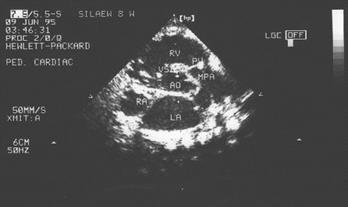

Это самый частый "синий" порок. Тетрада Фалло - это сочетание 4 признаков: стеноз легочной артерии вплоть до полного закрытия просвета, декстрапозиция аорты (аорта как бы сидит верхом на правом и левом желудочках, то есть сообщается с ними обоими), дефект межжелудочковой перегородки и гипертрофия правого желудочка. Сопровождается с раннего детства стойким цианозом.

Двухмерная ЭхоКГ:

1. Непосредственная визуализация дефекта межжелудочковой перегородки, смещения аорты и ее дилатации в парастернальной проекции длинной оси.

2.

Непосредственная визуализация стеноза легочной артерии, места его локализации и степени выраженности.

Непосредственная визуализация стеноза легочной артерии, места его локализации и степени выраженности.